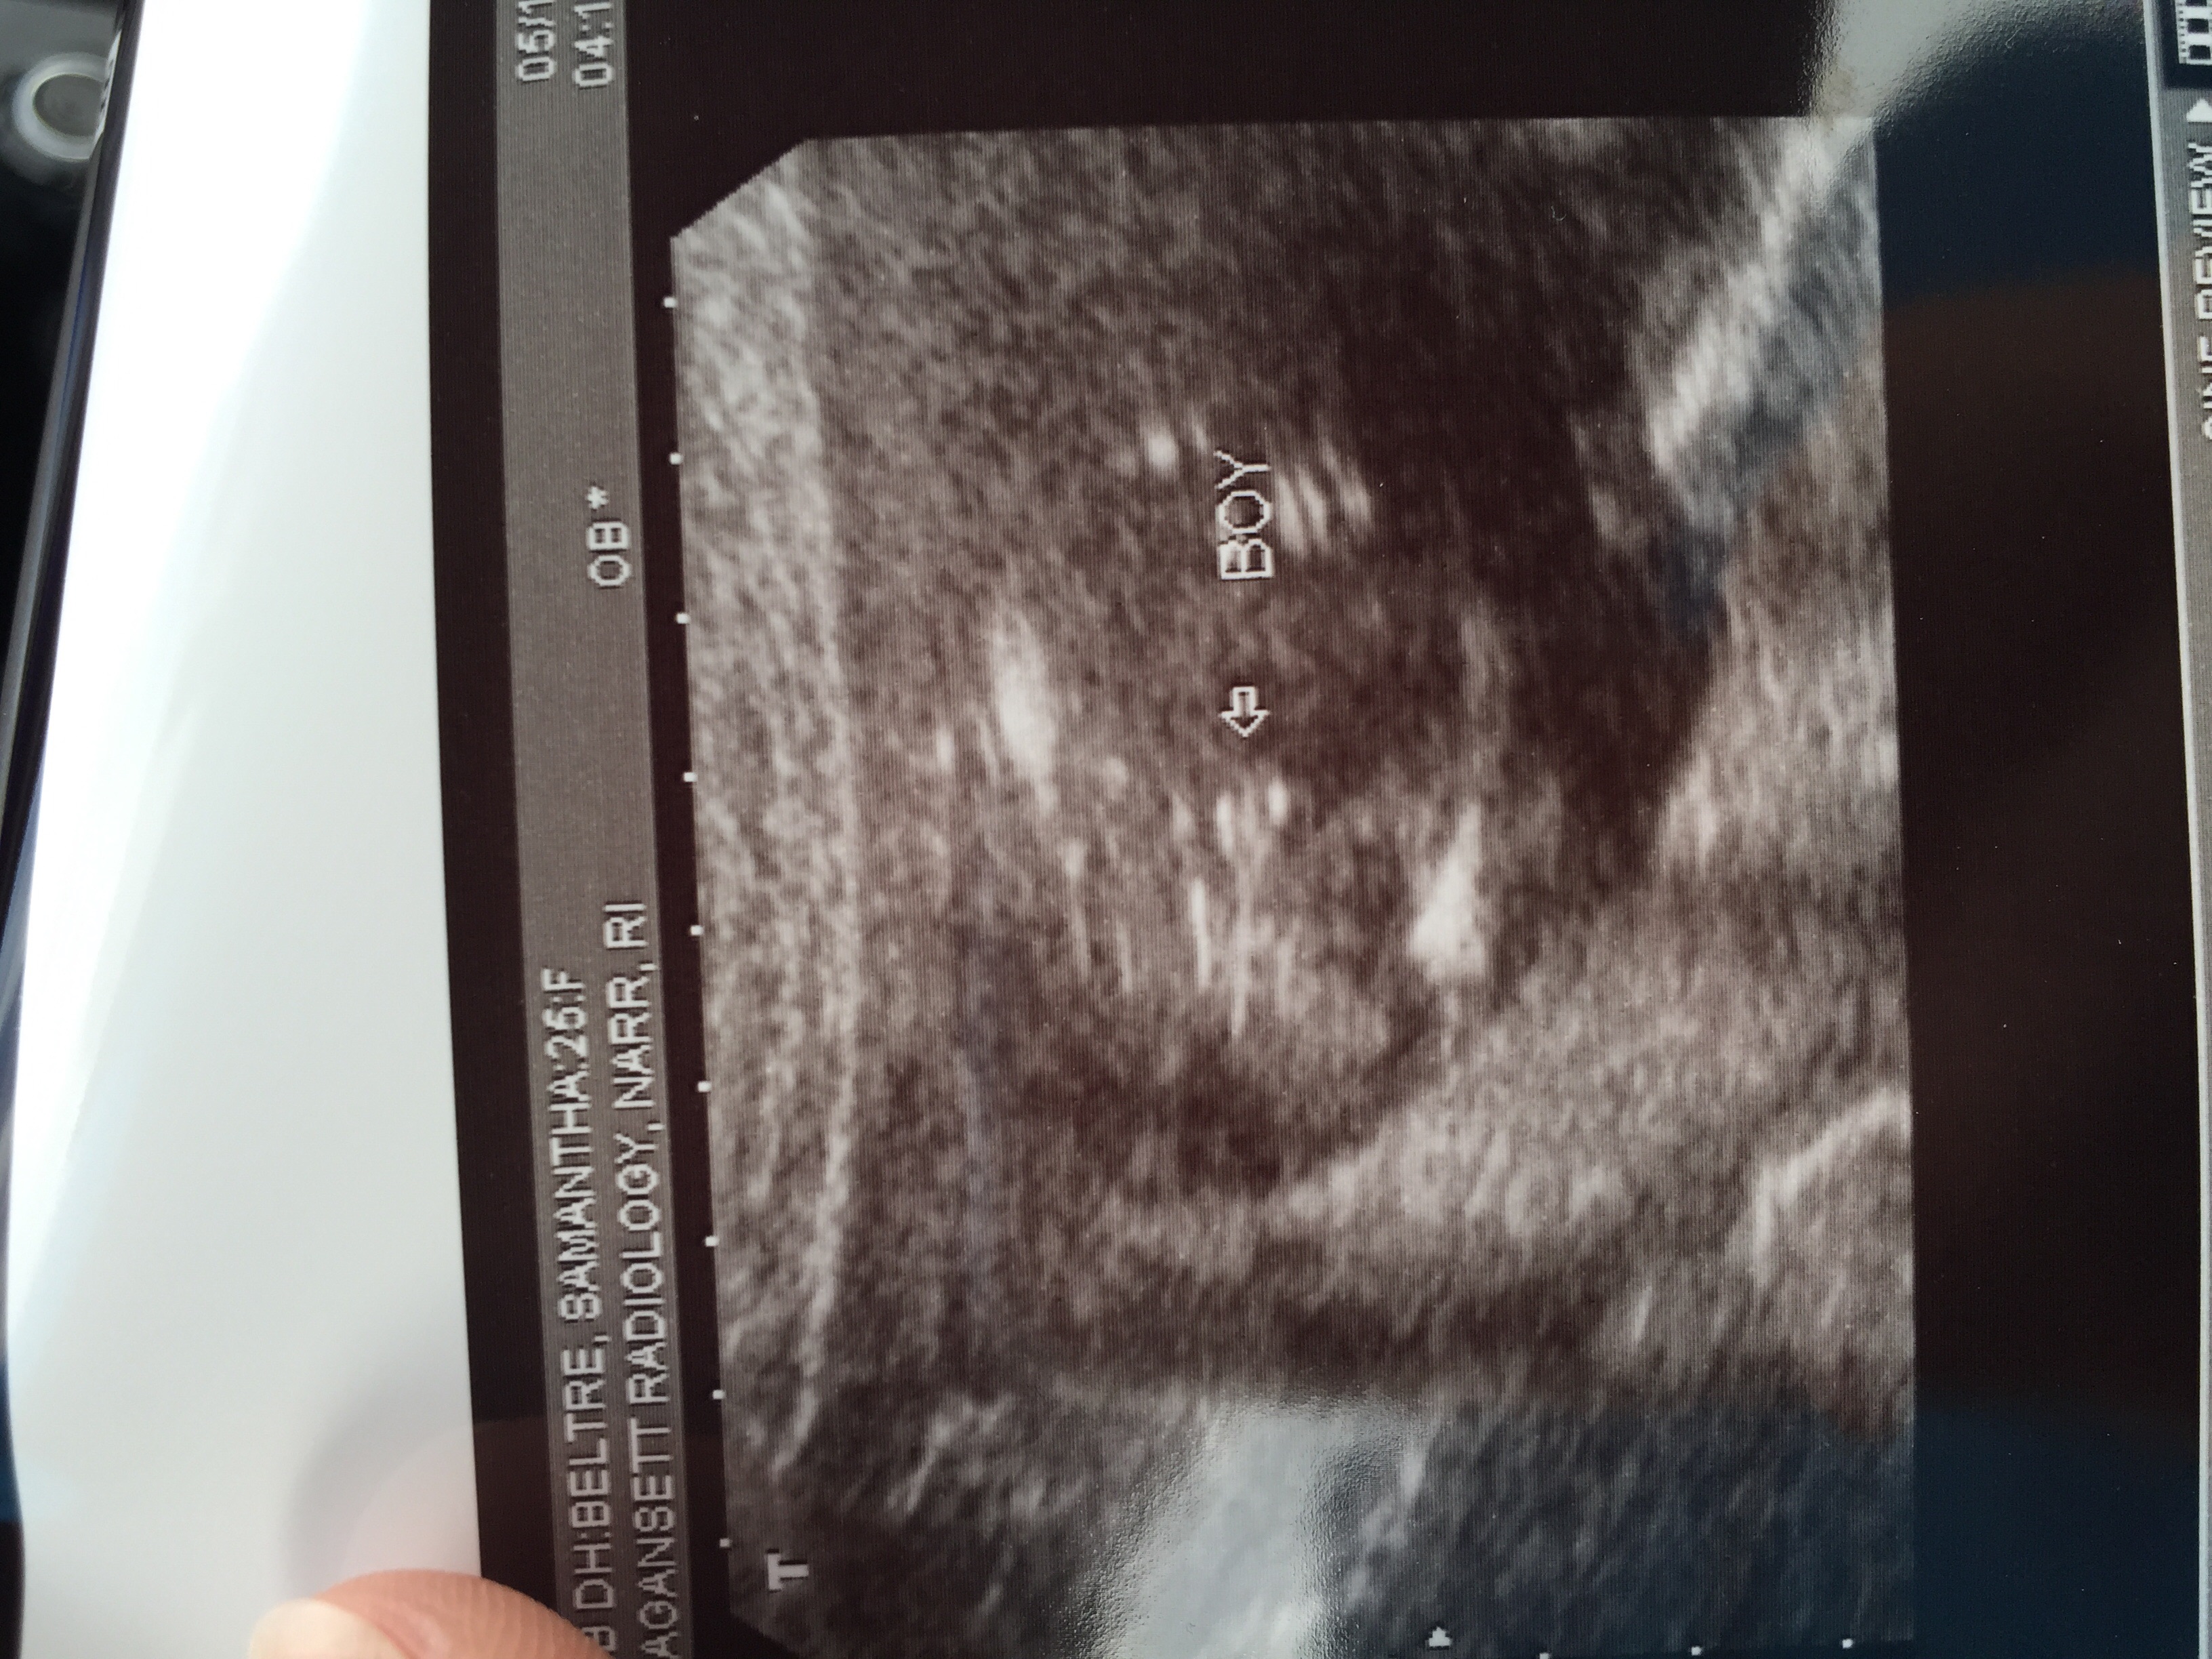

18 week ultrasound!

They confirmed he's still a boy!

The tech said he's measuring 81st percentile!!!

And everything looks normal! Coudnt be happier